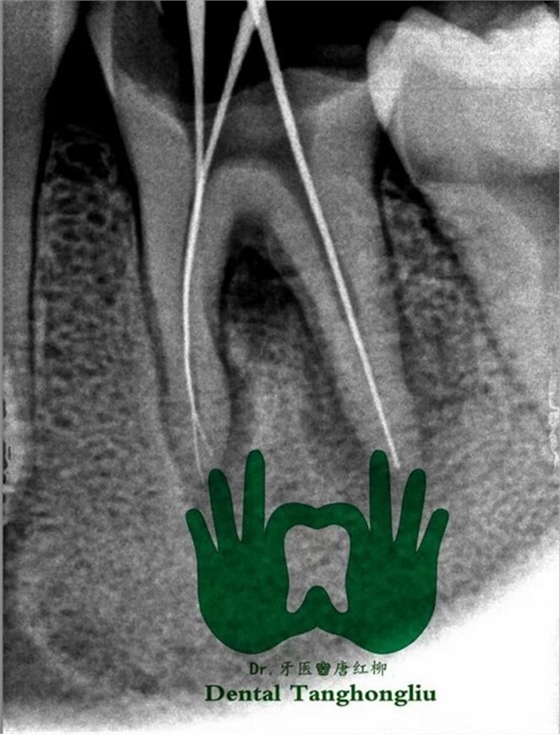

診斷、X片忽略,清潔患牙及鄰牙,對頜牙。

部分病例: